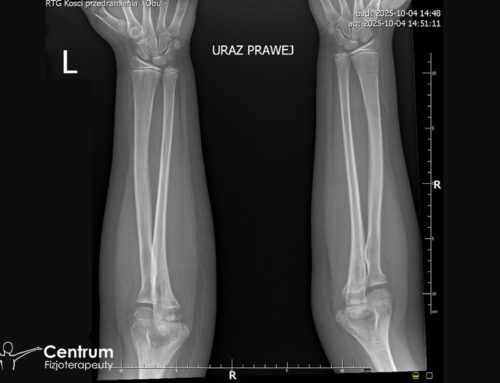

Złotym standardem diagnostyki uszkodzeń łąkotek jest rezonans magnetyczny. Widać na nim z dużą dokładnością lokalizację, rodzaj, wielkość uszkodzenia łąkotki, ale także stan więzadeł, kości, mięśni, chrząstki stawowej, rzepki. Tym samym można precyzyjnie ustalić dalsze postępowanie. RTG nie ma zastosowania przy urazach łąkotkowych i innych tkanek miękkich.